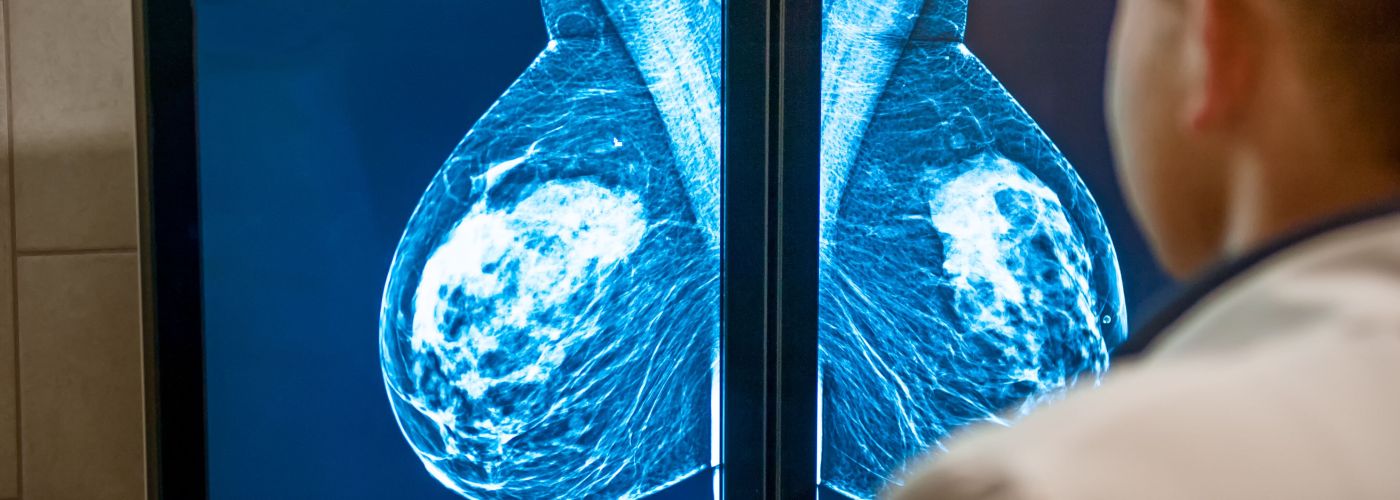

Artificial intelligence (AI) is rapidly transforming radiology by enhancing image interpretation and increasing detection of abnormalities, including subtle or early-stage findings. However, Inflo Health CEO Angela Adams’ article in Onco’Zine spotlights a critical and often overlooked consequence of this technological leap: the unintended risks of over-detection.

While AI tools improve sensitivity, they also identify many incidental findings—some clinically irrelevant, others ambiguous—which can lead to a surge in follow-up tests, unnecessary procedures, patient anxiety, and escalating healthcare costs. This raises a paradox: detection without context can result in more harm than good.

One major concern is the increase in false positives and overdiagnosis, particularly for findings that wouldn’t have progressed to harm if left alone. Radiologists and care teams are placed in a challenging position—navigating a sea of flagged results without a clear sense of clinical urgency or impact.